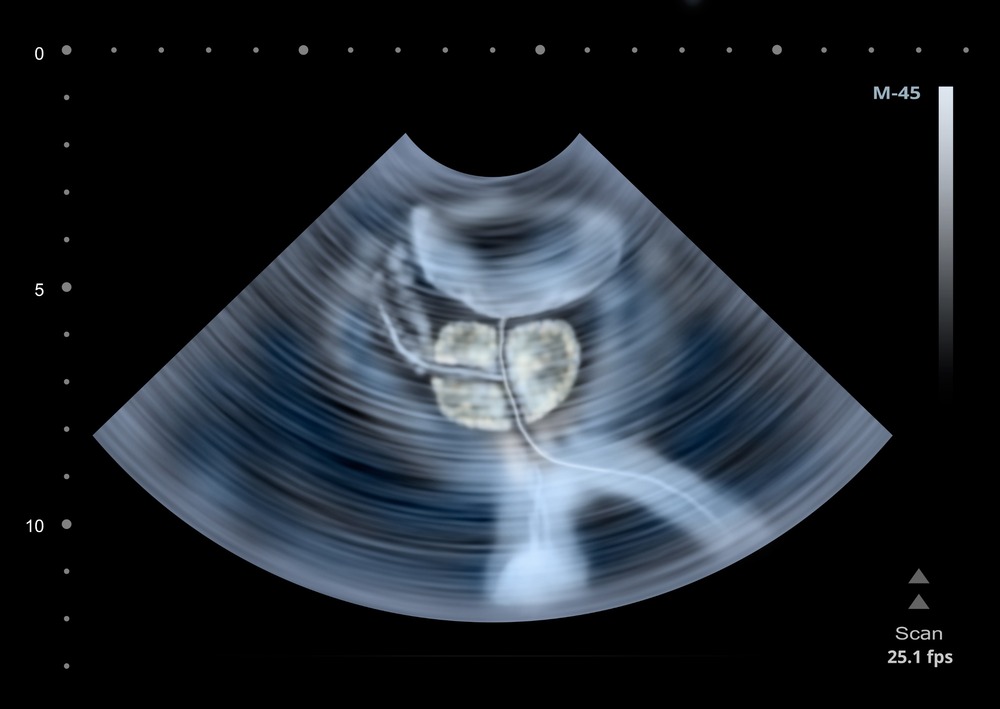

A prostate scan is a non-invasive imaging procedure used to examine the prostate located in the lower abdominal cavity. It also assesses the bladder, measuring its volume before and after emptying, as well as the prostate and seminal vesicles.

A transrectal prostate ultrasound uses a small probe (camera) that is inserted into the rectum for having a closer look at the prostate for medical imaging to check the prostate inside your lower abdominal cavity. This includes bladder with the measurement of bladder volume before and after emptying, prostate, and seminal vesicles.

Prostate ultrasound is a non-invasive (except transrectal scan for the prostate in which a small probe (camera) is inserted into the rectum for having a closer look at the prostate) medical imaging to check the prostate inside your lower abdominal cavity. This includes bladder with the measurement of bladder volume before and after emptying, prostate, and seminal vesicles.

The prostate is an organ located beneath the urinary bladder. It is roughly the same size and shape as a walnut and increases in size as one ages. The prostate is located around the urinary bladder, which is a tube that transports urine from the bladder to the urinary bladder. The primary purpose of the prostate is to facilitate the production of seminal fluid, the liquid that carries sperm.